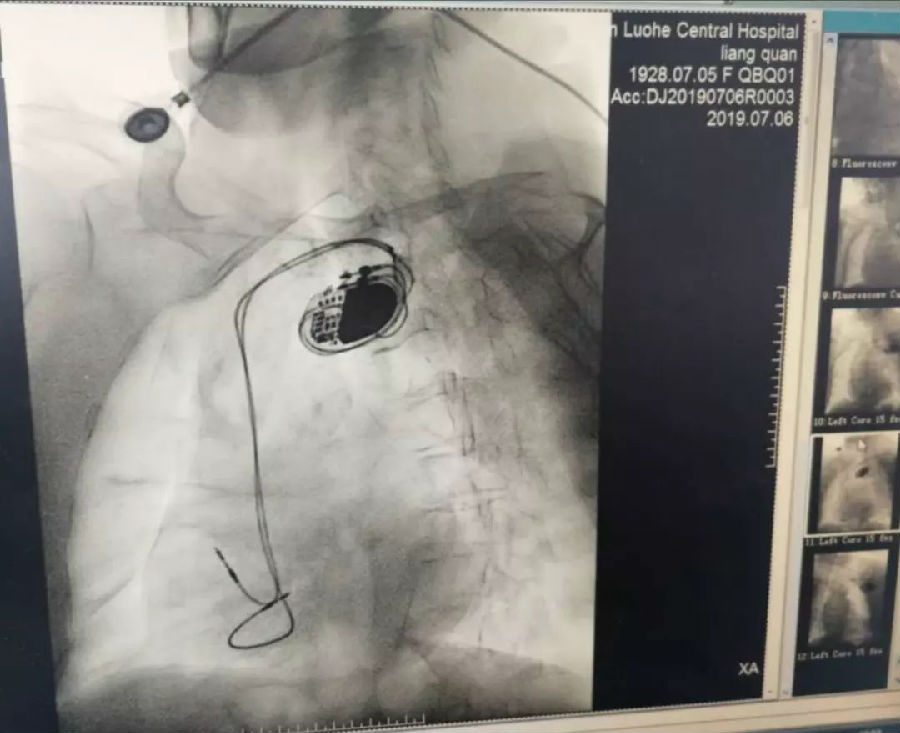

7月6日,我院心内科电生理团队用时40分钟成功为一位91岁高龄老人安装了永久起搏器。

7月6日上午9点,医院工会主席、心内科学科带头人刘东亮教授带领心内科电生理团队开始行永久起搏器植入术,9点40分成功植入永久起搏器,患者安返病房。从手术开始到结束用时仅40分钟,术中对起搏器进行程控,参数满意,术后疗效显著,患者病情平稳,血压恢复正常,自诉其他不适症状在不断的好转,目前正在恢复中。